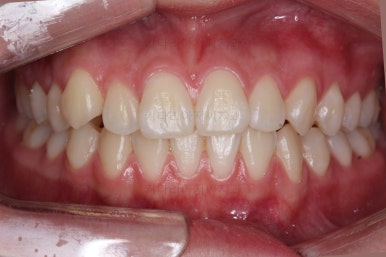

각설하고 위의 사진들은 부산치아교정잘하는곳 키다리아저씨치과에서 처음 내원하셨을 때의 사진입니다.

그리고 오른쪽 위 송곳니가 덧니처럼 볼록하여 웃거나 말할 때 자신감 있게 입을 벌리지 못하고 있었어요.

아랫니는 크게 심하지 않았고 윗니 앞니쪽에 치열이 삐뚤한 것을 볼 수 있어요.

그리고 위아랫니의 중앙선도 어긋나 있는 것으로 봐서 왼쪽과 오른쪽의 교합 자체도 다르고 문제가 있음을 알 수 있었어요.